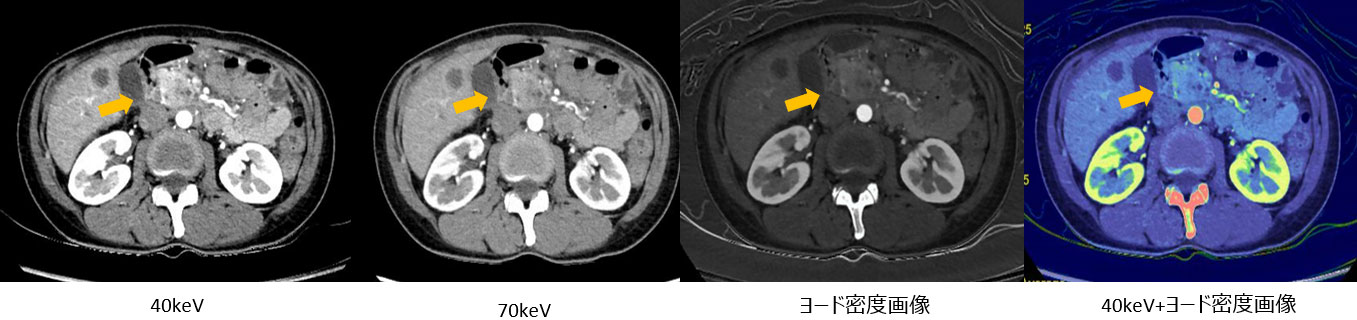

・早期膵臓腫瘍(Fig8) の描出を目的に低keV画像を用いた撮影

RevolutionCT_Minamitohoku09.jpg

Fig8, 低keVを用いた早期膵腫瘍の描出